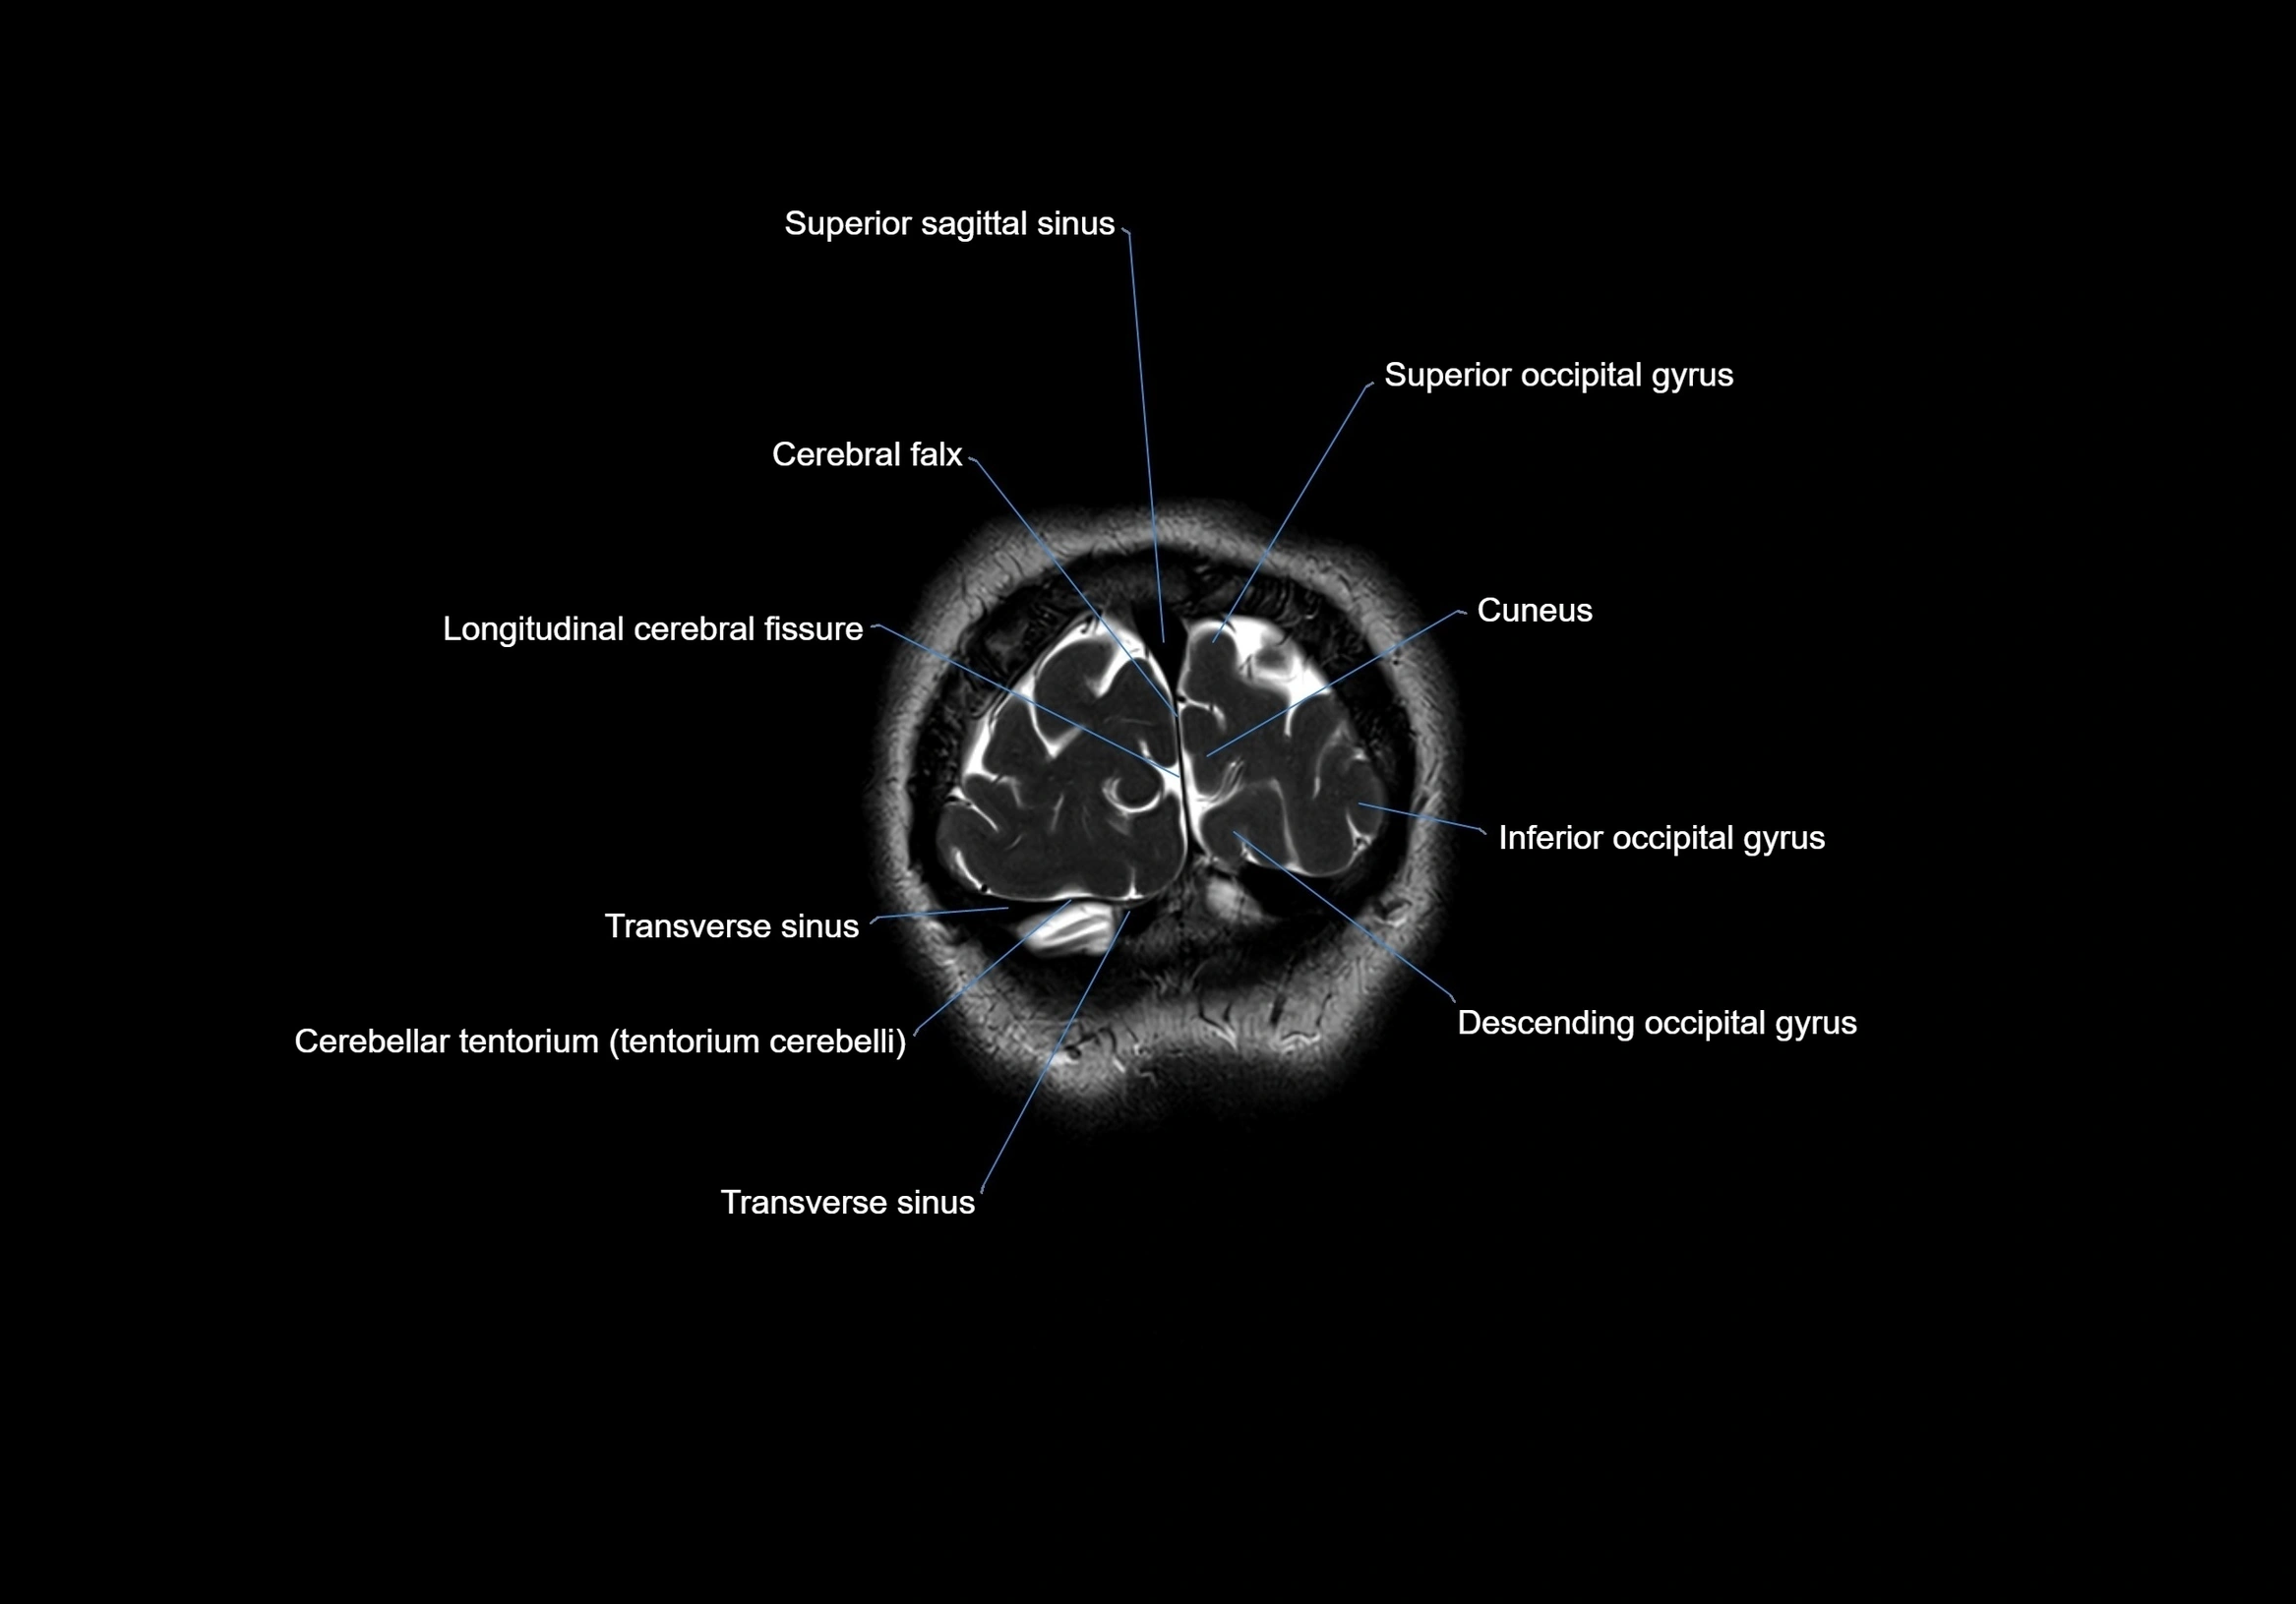

MRI images